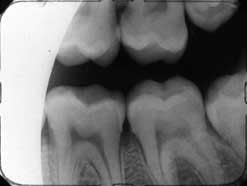

When taking X-rays in the lower arch, the arch must be parallel to the floor. It is very difficult to take good X-rays when the patient is in a reclining position. Instead, always seat the patient in an upright position to facilitate positioning of the arch being X-rayed so that it is parallel to the floor.

Place the films in the Styrofoam holder and place the films opposite the teeth to be viewed for the bicuspid and molar X-ray. Pre-set the angle of the X-ray head at -10 degrees for the bicuspid view and -5 degrees for the molar view, following the same technique described for the upper arch. Bitewing films are placed in the film bite holders and are placed in a similar manner for the bicuspid view and then the molar view, and the angle of the head is set at 5 to 10 degrees.

Occasionally, during radiographs of the lower arch, the corners of the film feel like they are digging into the sensitive tissues of the floor of the patient's mouth. There are two ways to address this. You can choose a film packet with a cushioned edge such as Kodak SureSoft™ packets. It is also helpful to get the patient to relax because the floor of the mouth will be more flexible and accommodate the film packet more easily.

One of the most common errors is due to improper placement of the films in the arch to be X-rayed. We frequently see X-rays mounted in the posterior regions where the bicuspid and the molar views are identical, or the right lateral and central incisor are missing, and there are two views of the two central incisors. Placement of the film is of paramount importance for the success rate of diagnostic quality films. If you do not place the films in the correct position, the shadow will be cast only on those teeth in front of the misplaced film.

Similarly, if the head of the X-ray machine is facing distally or mesially instead of parallel to the film or average face of the tooth or teeth, the result will be overlapping, cone cutting, and missing parts of the teeth needed for proper diagnoses. The film edge being held by the Styrofoam holder must follow the occlusal plane. If the film is crooked, the result will be an X-ray that is improperly positioned.